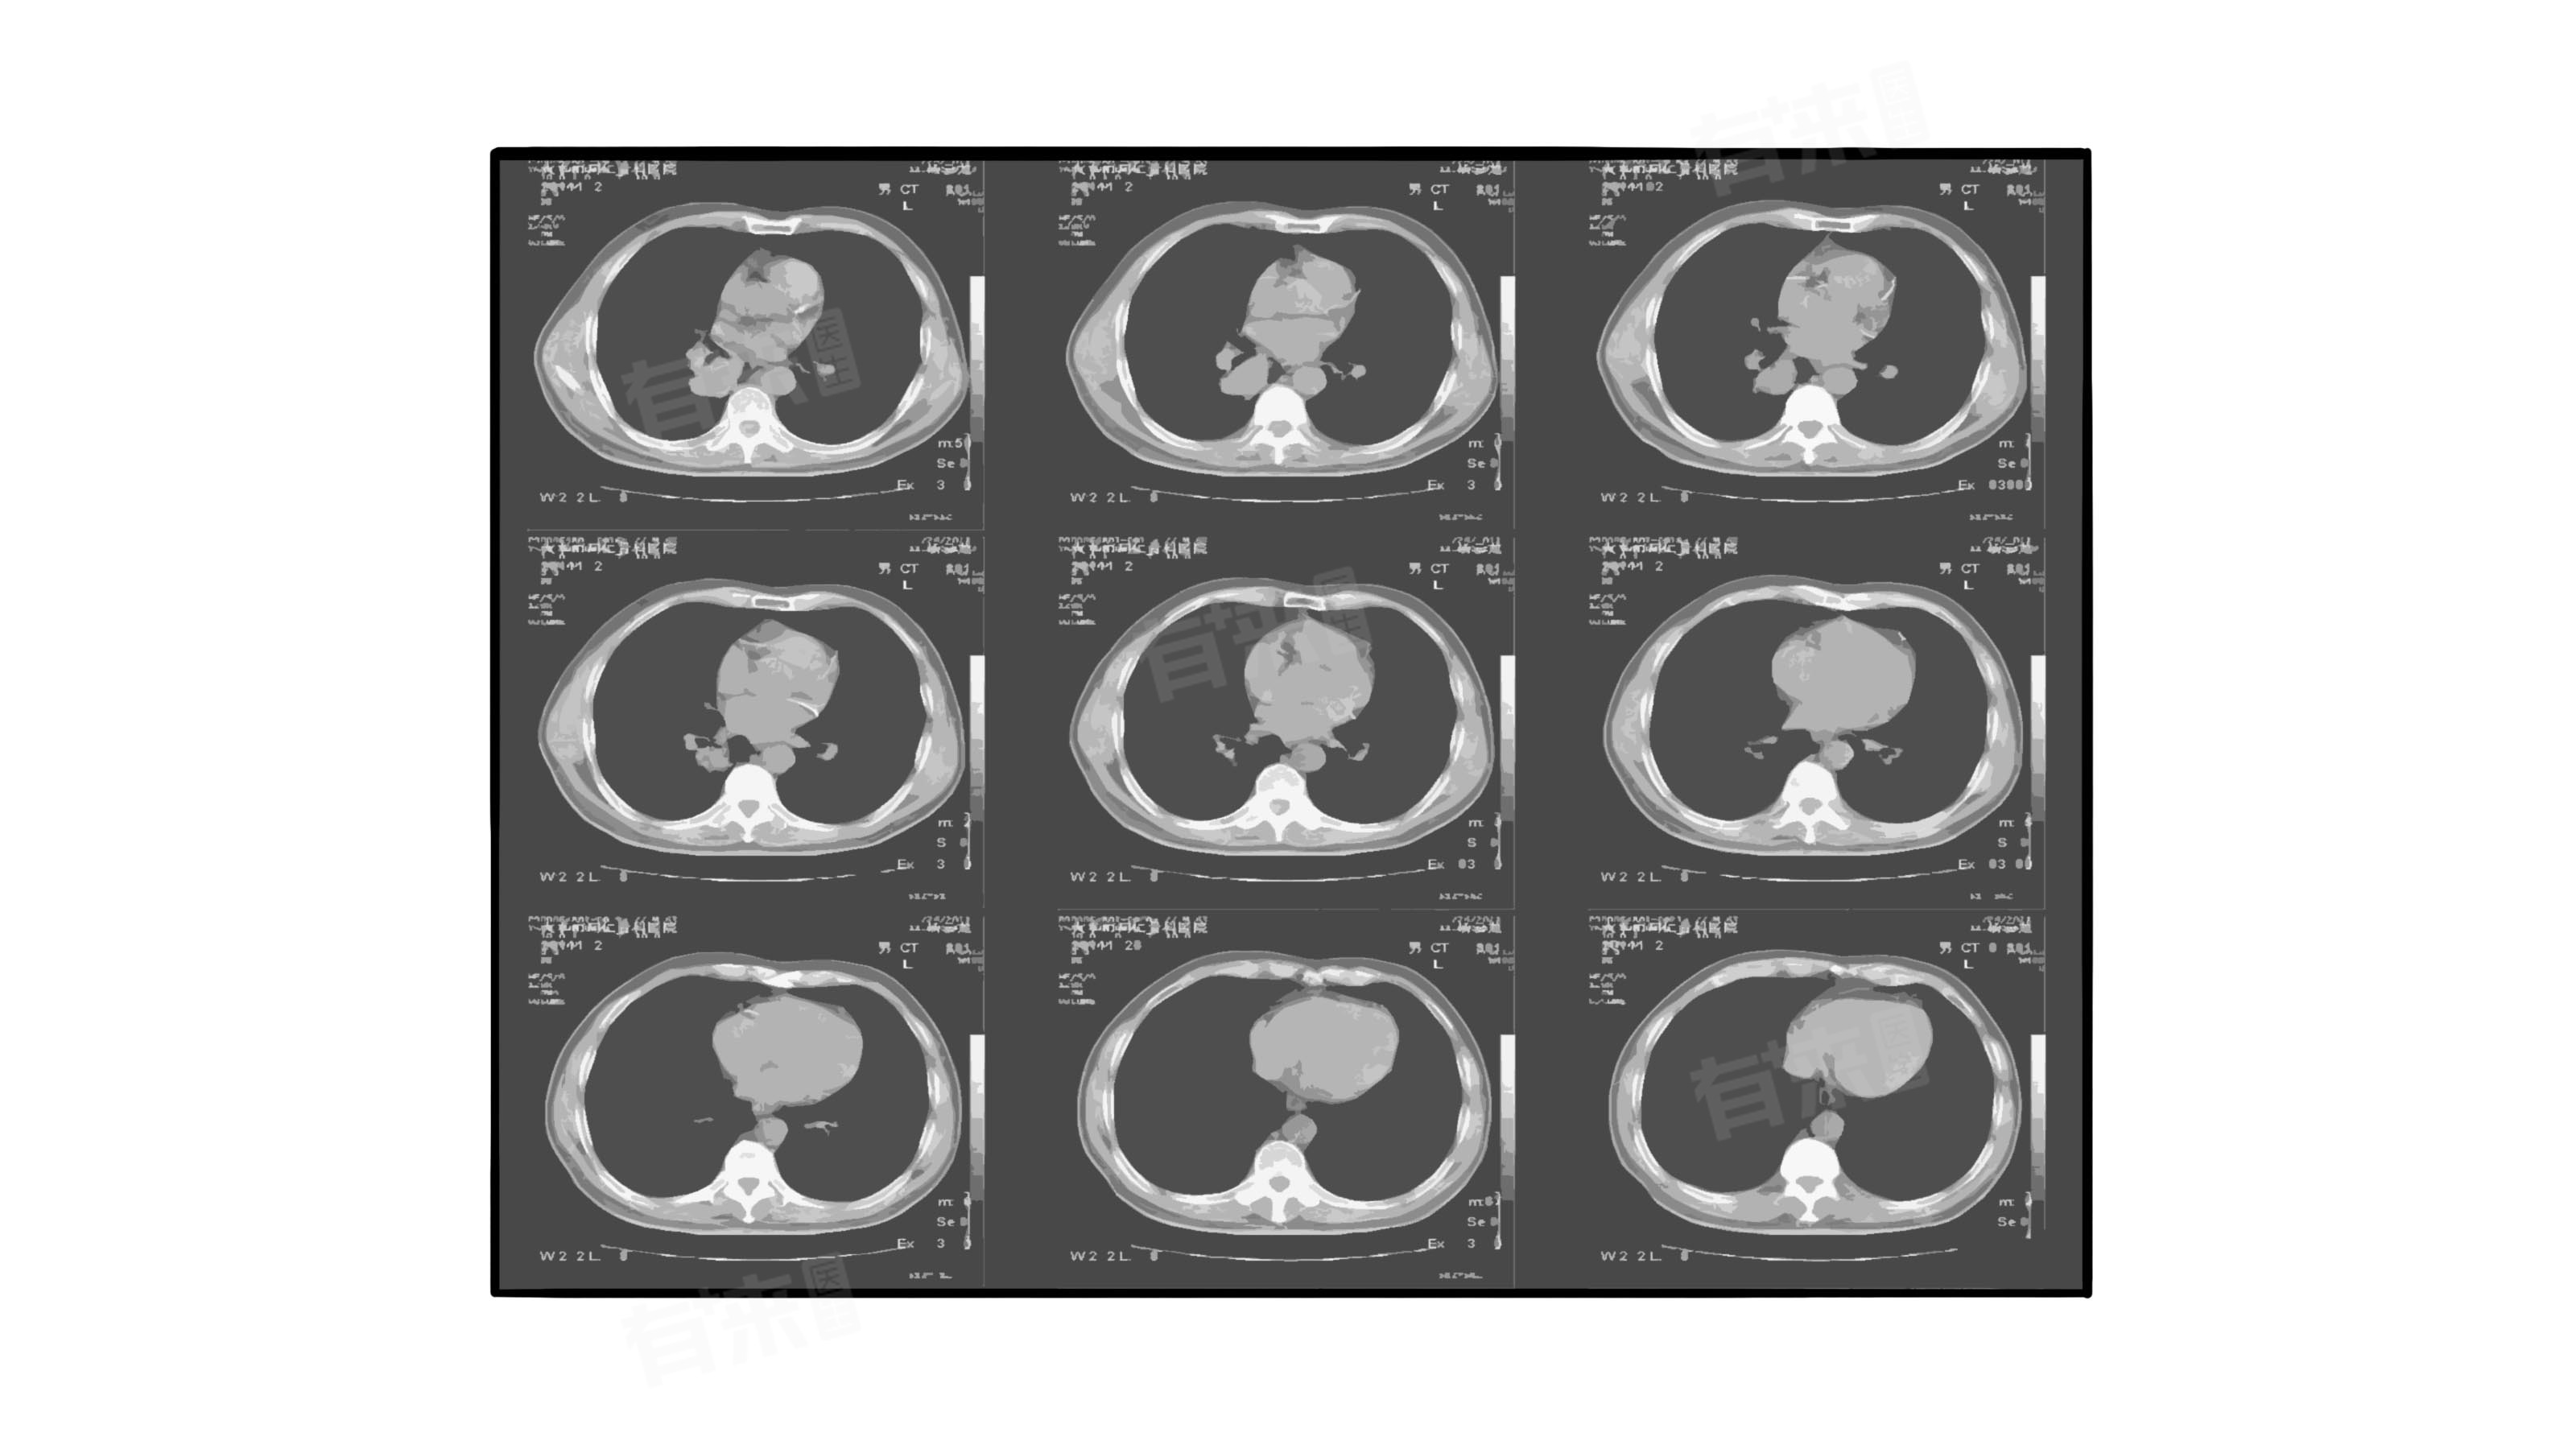

左肺叶磨玻璃结节是指在胸部影像学检查(如胸部CT)中,发现左肺叶上存在密度轻度增高的云雾状淡薄影,其密度不足以掩盖其中走行的血管和支气管影,类似磨砂玻璃样的表现,这种结节的出现主要由长期吸烟、肺炎、肺结核等原因引起。